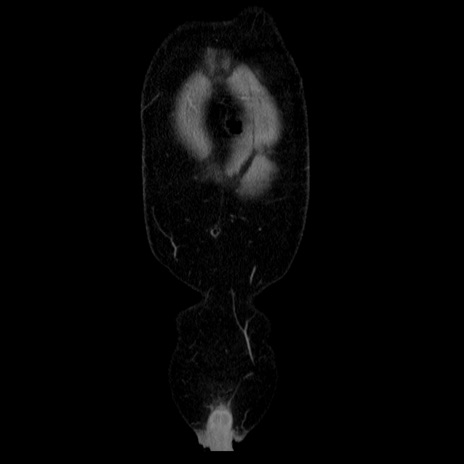

横断像

【症例】40歳代男性

【現病歴】2日前から胃痛あり。徐々に周期的な激痛に変化した。本日になっても激痛があるため受診。

【身体所見】意識清明、BT 38-39℃台あり、腹部:膨満、やや硬、右下腹部に圧痛あり。

【データ】WBC 8500、CRP 23.26